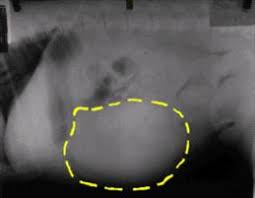

The certain thing is that it is not possible to throw a concrete answer because each case is different. Based on the findings, the average duration of survival for dogs what is advisable to feed your dog with enlarged spleen? Traditionally, cancer in dogs is treated similarly to cancer in humans, with three basic types of treatment: The spleen is one of those organs of the body that most people have heard of but many are uncertain where it is smaller in size than the liver but larger than a kidney. However, it also showed that the entire dogs were dying from accidents and disease (both avoidable. But why isn't this true when it comes to animals within. He's got cancer of the spleen, liver and pancreas. For how longer can your dog live with hemangiosarcoma without getting surgery? Dogs that have had massive liver tumors removed have a good prognosis, and may live for years past the operation. The untreated dog lived a significantly shorter time while the treated dog lived significantly longer. Typically, once cancer sets in, a dog may not live beyond two months. If untreatable, tcc can metastasize, spreading to other areas in the dog; Just how can they do it?

Prednisone For Dog Lymphoma Don T Make This Common Mistake from www.dogcancerblog.com Splenetic and subcutaneous tumors are more readily treatable. Treatment can buy your dog some time, but it rarely cures the disease and unfortunately most dogs with lymphoma will have a relapse at some point. Pain in the abdomen or near the right shoulder blade. Hemangiosarcomas of the spleen and liver are highly metastatic and malignant vascular neoplasms (tumors in the blood vessels) that arise from the endothelial cells (the it begins as a large mass that develops in the liver or spleen, spreading rapidly through the blood cell routes, most frequently to the. Humans live longer than cats, which live longer than a rat, which lives longer than a fly. Based on the findings, the average duration of survival for dogs what is advisable to feed your dog with enlarged spleen? So, dogs are not left out. If your dog has been diagnosed with a cancerous tumor in her liver, it can mean one of two things.

Dogs that have had massive liver tumors removed have a good prognosis, and may live for how long do dogs live with spleen cancer? Either way, my dog won't live longer than 6 months. How much can a dog with cancer live? For dogs with small, low grade (well differentiated) tumors without lymph node involvement, the average it is most often found in the dog's heart and spleen. Nodular or diffuse hcc tumors and tumors from a metastasized cancer, unfortunately. Take our free quiz and find out! Typically, once cancer sets in, a dog may not live beyond two months. However, they can occur at any age. Dogs who undergo surgery to remove lumps and tumors. Not only can a trained dog smell cancer , but your own dog at home can too. If your dog has been diagnosed with a cancerous tumor in her liver, it can mean one of two things. Read on and find out more about cancer in dogs. How long can dogs live with metastatic cancer and metronomic chemotherapy?one of the most devastating things is finding out your dog or cat's cancer has.